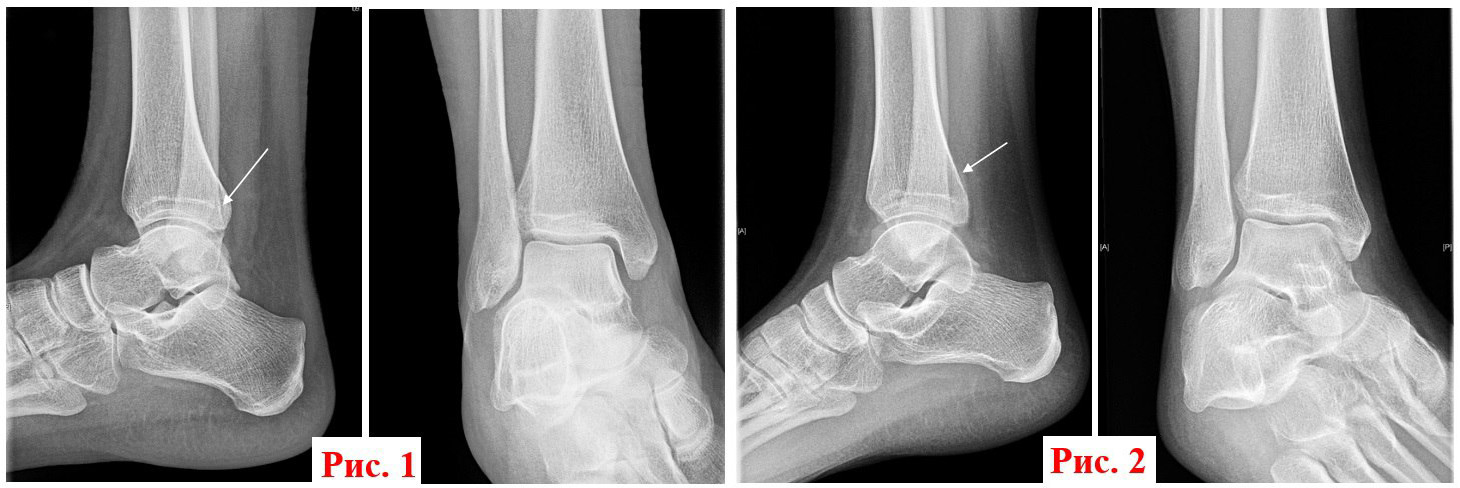

• На рентгенограммах правого голеностопного сустава: перелом заднего отдела правой большеберцовой кости без смещения отломков (рис. 1).

3 недели спустя провели контрольный рентген правого голеностопного сустава (рис. 2). Консолидированный перелом задней лодыжки (костная мозоль - стрелка). Пациент уверенно идет на поправку. А мы уверены, что причину любых жалоб можно найти, особенно когда за дело берутся профессионалы, а помогает современное оборудование.